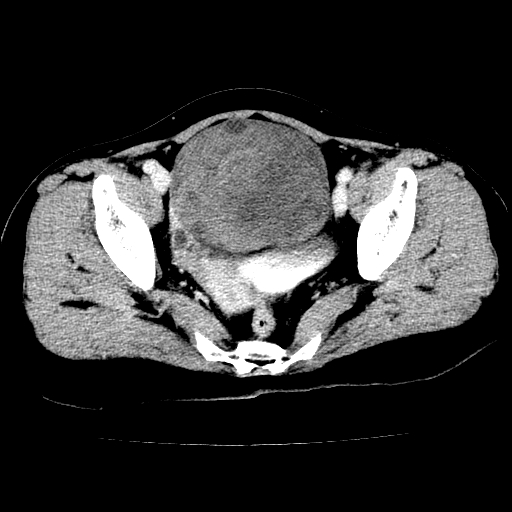

标题: CT24785:女,62岁,发现下腹部肿物半年。 [打印本页]

标题: CT24785:女,62岁,发现下腹部肿物半年。

女,62岁,发现下腹部肿物半年,下腹部不适。

考虑回肠间质瘤,不排除卵巢癌可能。

该年龄性别首先考虑平滑肌肉瘤可能性大,其他待排除。